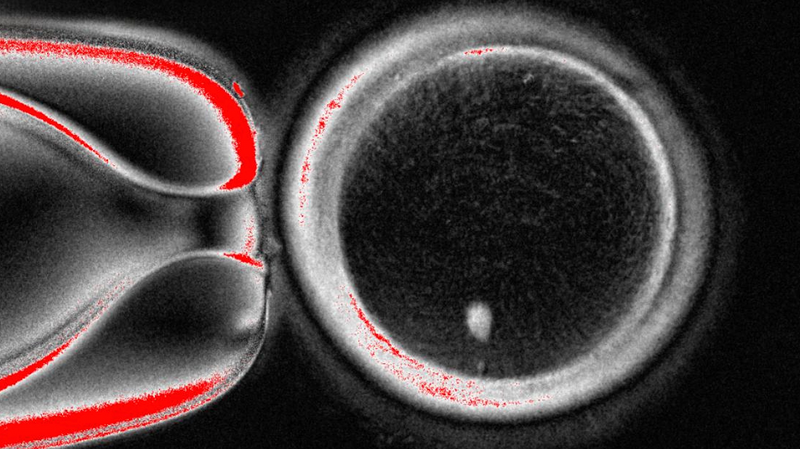

Skin cells normally carry 46 chromosomes (two sets), but eggs need just 23. Scientists at Oregon Health & Science University cracked this puzzle with mitomeiosis—a new cell division method that discards extra chromosomes. 🎯 'We achieved something thought impossible,' said lead researcher Shoukhrat Mitalipov.

In lab tests, only 9% of fertilized eggs reached the blastocyst stage (70-200 cells), and none developed further. Many showed chromosomal abnormalities. Still, experts call it a 'huge leap' for reproductive science. 'This could redefine how we treat infertility,' said UK specialist Ying Cheong.